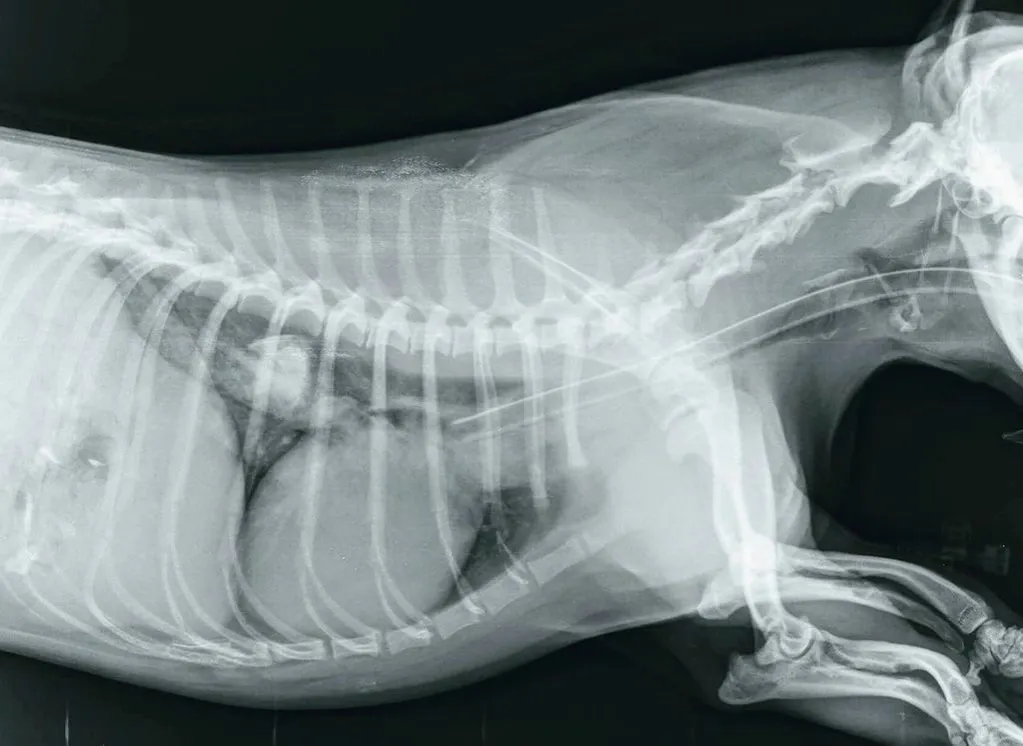

W przypadku zaobserwowania któregokolwiek z tych objawów, natychmiast skontaktuj się z weterynarzem. Lekarz prawdopodobnie zleci badanie RTG, aby zlokalizować kość i ocenić ryzyko, a następnie podejmie decyzję o dalszym postępowaniu.